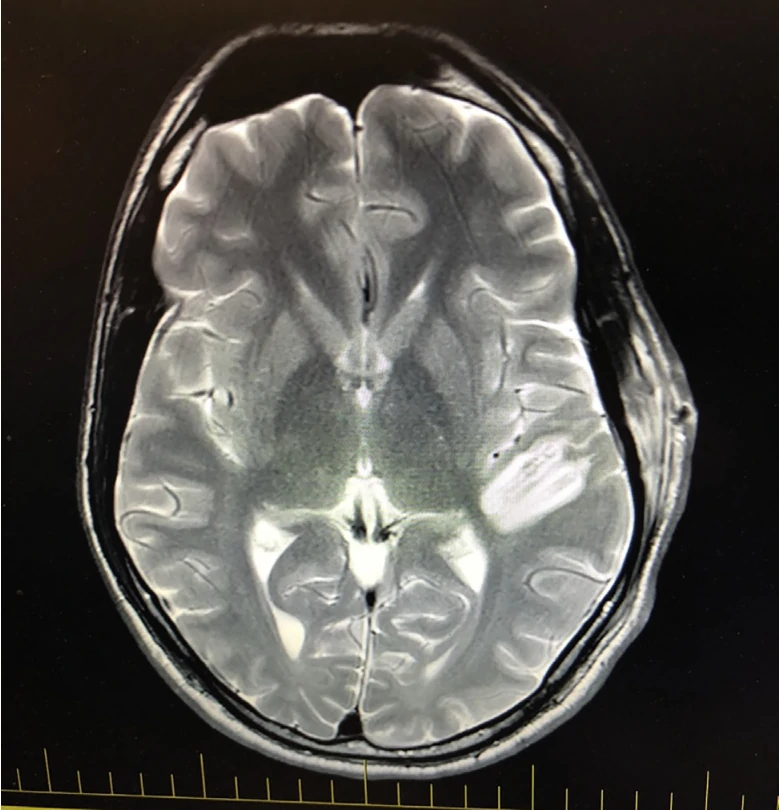

局部消融左脑汞柱而未损伤前脑汞柱对言语感知和语言理解无影响

磁共振(MR)图像显示手术消融的范围沿HG轴向,而对pSTG没有影响。图像以放射方向显示。